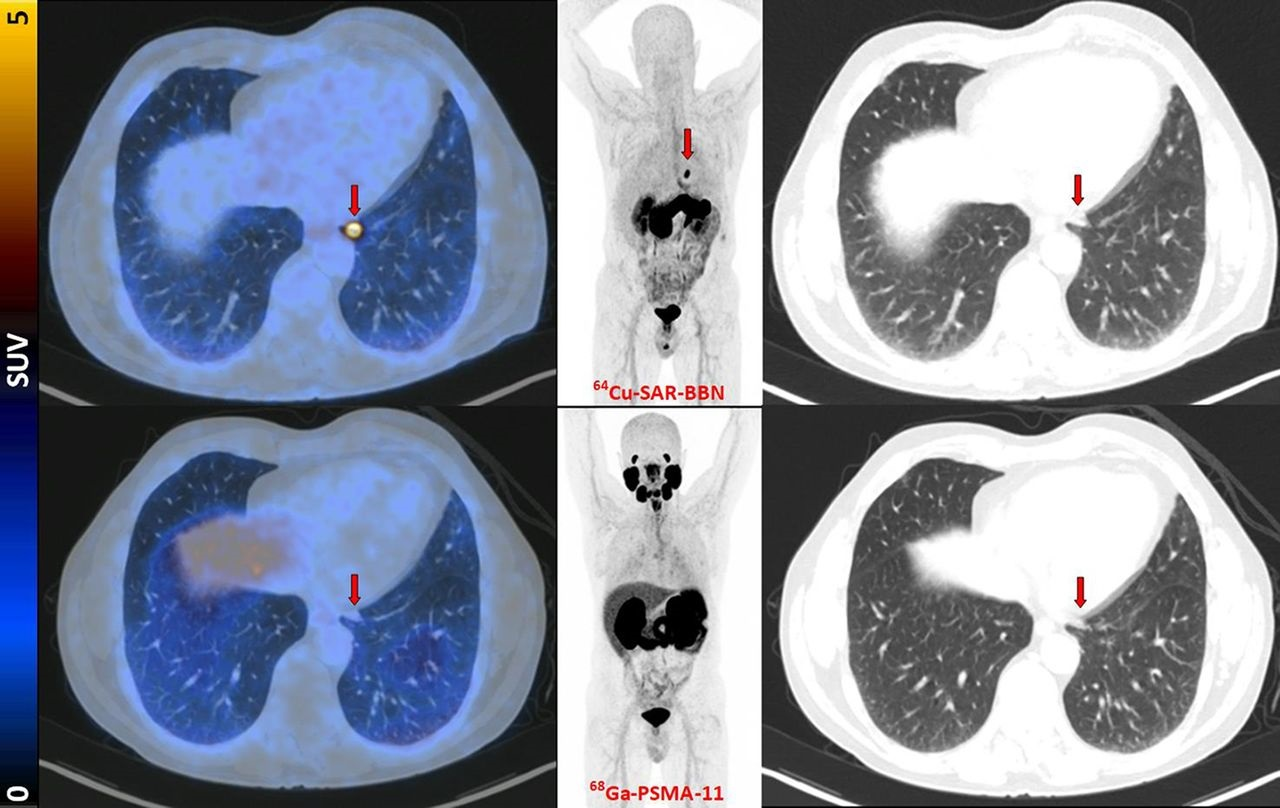

Radiopharmaceutical firm Clarity Pharmaceuticals said that its copper-64 SAR-Bombesin (SAR-BBN) agent has been used in the first patient of its Copper-64 Bombesin in Breast Cancer Trial (C-BOBCAT).

C-BOBCAT is the first in-human clinical trial investigating the use of the radiopharmaceutical in patients with hormone-receptor-positive/HER2-negative metastatic breast

cancer, according to the company. The trial is being led by Dr. Louise Emmett of St. Vincent's Hospital in Sydney, Australia.

"We hope that SAR-BBN will allow for [PET] imaging and localization of metastatic breast cancer lesions that express [gastrin-releasing peptide receptor (GRPr)], and we look forward to utilizing that data to progress SAR-BBN into other diagnostic and therapeutic trials in a range of cancers that express GRPr with our ultimate goal of better treating children and adults with cancer," said Clarity CEO Alan Taylor, PhD, in a statement.